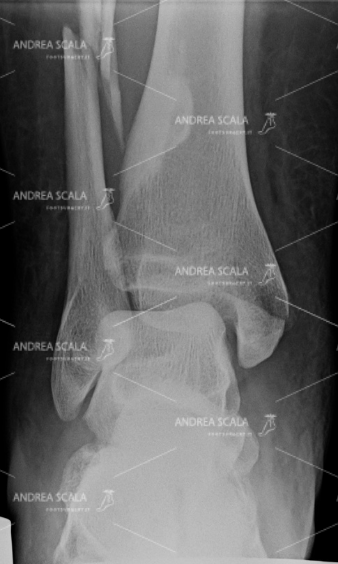

La RXgrafia anteriore mostra la frattura tri-malleolare con lesione della capsula e dei legamenti. Una giovane paziente ha subito questa grave frattura a 34 anni.

La RXgrafia laterale mostra la frattura tri-malleolare con lesione della capsula e dei legamenti. Si nota la grave scomposizione della frattura. In questi casi si deve capire che lo schiacciamento subito dalla cartilagine è inevitabile.